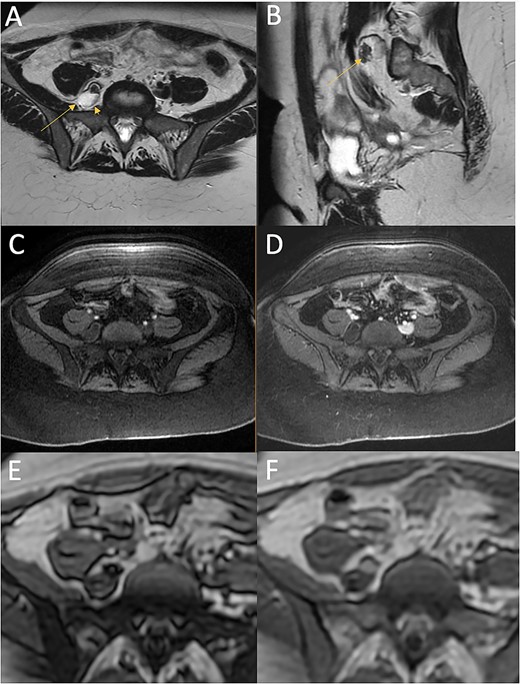

T2 (A, axial; B, sagittal) and T1-weighted with fat saturation (C, axial pre-contrast; D, axial post-contrast), T1 dixon (E, axial in-phase; F, axial out-of-phase) images from the MRI of the pelvis at presentation. The heterogeneous complex cystic mass (arrow) is located lateral to the vertebral body and posterior and medial to the psoas muscle. It is characterised by predominantly high T2 signal, with a region of dark T2 signal anteriorly, low T1 signal on fat-saturated images. The anterior T2 dark component shows drop out on the out-of-phase imaging compared with the in-phase imaging indicating a component of fat. It abuts the right L5 nerve root (arrowhead).

An MRI of the pelvis showed a multilobulated lesion medial to the right psoas muscle measuring 2.6 cm × 1.7 cm, similar to her previous MRI 4 months earlier (Fig. 1). Based on the imaging, the differential diagnosis included hematoma, lymphatic structure, nerve sheath tumor or myxoma. Given her persistent and debilitating symptoms, the patient elected to undergo surgery for resection and diagnosis of the retroperitoneal mass.